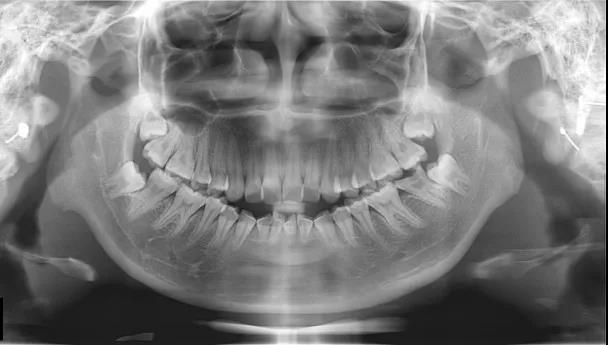

牙齿矫正,又称为正畸,是通过各种矫正装置来矫正牙齿畸形。

目前牙齿矫治分为三类: